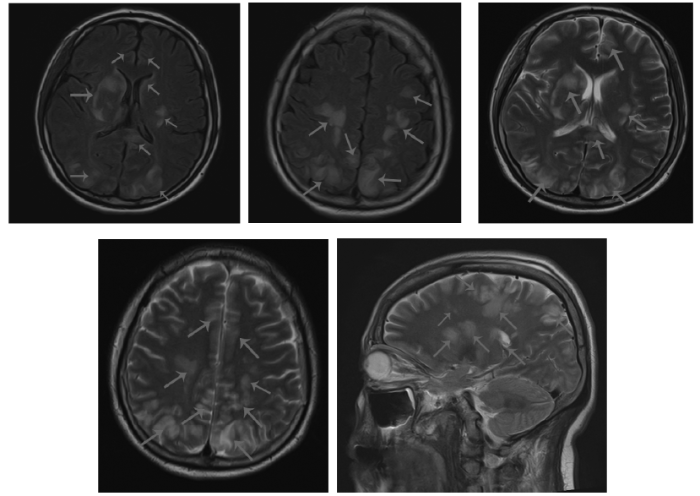

2021年9月30日04:40全身麻醉下行紧急子宫下段剖宫产术,成功娩出一男活婴,脐绕颈一周,体质量2 360 g,新生儿1 min、5 min、10 min Apgar评分分别为9分、10分、10分。因胎盘滞留,行徒手剥离术。术中出血600 mL,子宫体肌内注射卡前列素氨丁三醇250 μg并按摩子宫后出血减少。术后给予缩宫素静脉滴注(20 U,1次/d)促进子宫收缩;头孢美唑钠静脉滴注(2.0 g,每12 h 1次)抗感染;因术前血小板明显降低且失血较多,术后输注同型红细胞悬液2.0 U、血浆500 mL补充血容量;术后血压186/122 mmHg,给予硝酸甘油15 mg(5 mg/1 mL),以4 mL/h微量泵静脉泵入降压;为预防产后子痫,给予硫酸镁60 mL(2.5 g/10 mL),以4 mL/h静脉泵入解痉。头痛、失明症状请眼科、神经内科会诊,视力、眼底检查后考虑双眼视力骤降与颅内病变相关,建议根据病情尽快完善头颅磁共振成像(magnetic resonance imaging,MRI)、弥散加权成像、磁共振血管成像(magnetic resonance angiography,MRA)和磁共振静脉血管成像(magnetic resonance venography,MRV)。颅脑MRV示:右侧横窦显影稍浅淡;上矢状窦内散在小斑片充盈缺损,蛛网膜颗粒与其他待鉴别。颈部、颅脑MRA-时间飞越法(time-of-flight,TOF)示:左侧椎动脉稍纤细,余未见明显异常。头颅MRI示:脑实质内弥漫多发异常信号,考虑RPLS可能;全组副鼻窦慢性炎症(见图1)。

图1

患者入院头颅MRI图像

注:双侧额顶枕颞叶、小脑半球及双侧基底节区、脑桥见多发大小不等斑片等/稍长T1稍长T2信号,弥散加权成像等信号。箭头所示为异常信号处。

RPLS是一种表现为头痛、抽搐、视觉或意识障碍等,由血管内皮细胞功能障碍和高血压引起的血管源性脑水肿综合征,包括高血压引起的静水压升高、血-脑屏障完整性破坏导致的血管内皮细胞功能障碍[5,7]。本例患者病程中出现典型的精神、视觉症状,应与子痫、脑静脉窦血栓脑炎、肾上腺脑白质营养不良等疾病鉴别。RPLS的症状一般在3个月内完全消退,预后良好,少部分患者可发生不可逆性神经系统功能障碍。MRI是RPLS诊断的金标准,孕产妇RPLS与非孕产妇表现无明显差异,多见双侧顶叶及枕叶的皮层下白质片状异常长T1和T2信号,弥散加权成像可见异常低信号,偶见于额颞叶皮层下白质、基底节区、脑干或小脑部[8]。本例患者头颅MRI检查示:双侧额顶枕颞叶、小脑半球及双侧基底节区、脑桥见多发大小不等斑片等/稍长T1稍长T2信号。妊娠相关RPLS的治疗关键在于对症治疗及针对脑水肿、脑血管内皮细胞损伤的病因治疗,适当应用硫酸镁、抗癫痫药物(如地西泮、苯巴比妥)。本例患者给予脱水、降压、镇静等治疗后视力恢复。但在使用皮质类固醇激素与否的问题上仍存在争议[9⇓-11],本例患者因肝肾功能损害、维持尿量等曾使用激素冲击治疗,但对于合并脑出血者应避免使用。